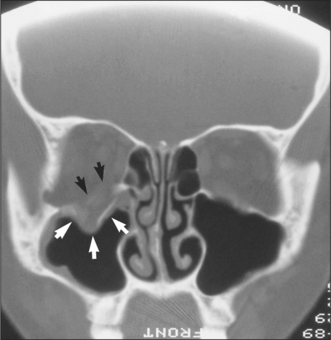

tooth-bearing areas of the jaws: orthopantomogram and posteroanterior (Figs 13.7, 13.8)

nasoethmoidal region and orbits: coronal computed tomography

Fig. 13.8 PA view of the jaws, showing a fractured mandible.

Radiographs may be necessary not only to reach a diagnosis but also to inform treatment decisions, for example, about where bone plates should be applied. They also commonly reveal injuries which may not need treatment, for example, undisplaced or minimally displaced fractures, medial blow-out fractures of the orbit and comminution of the mid-face. Radiographs provide much more detailed information on hard-tissue injuries than the clinical examination so they may, for example, show fractures of the roots of teeth and signs of associated soft-tissue abnormality, such as herniation of orbital contents into the maxillary antrum (Figs 13.9, 13.10).

Fig. 13.10 CT scan showing herniation of orbital contents (white arrows) through an orbital floor fracture. The inferior rectus muscle is highlighted with black arrows.